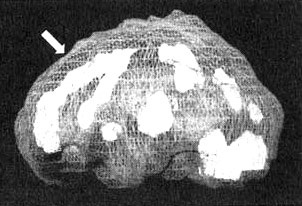

Мозг «яростного водителя»

Трехмерное изображение — активный мозг. Обратите внимание на выраженное усиление активности в поясной извилине (см. стрелку).